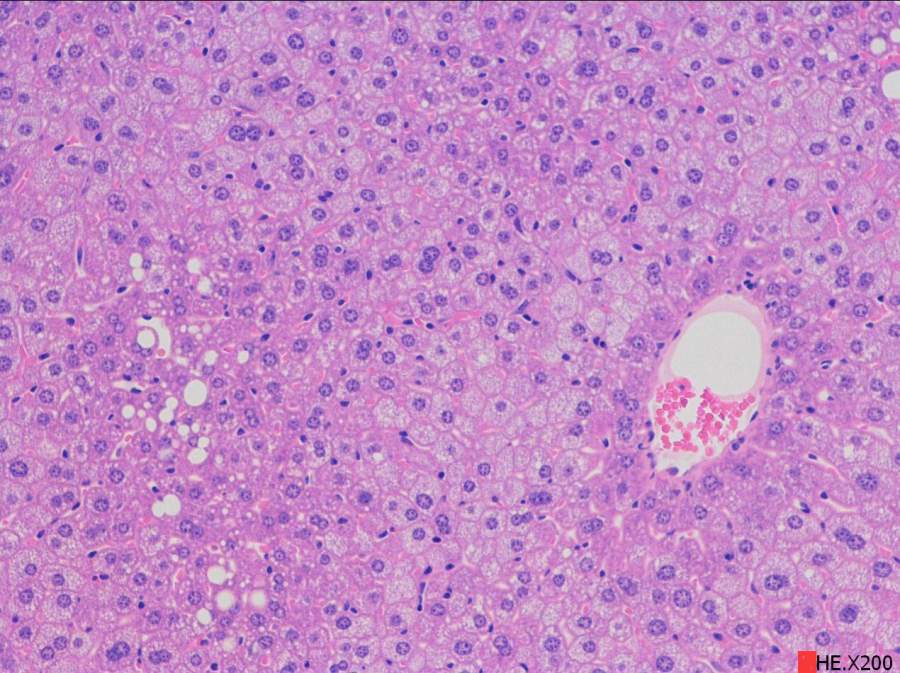

求助读片:小鼠肝脏HE切片(脂肪变性、炎症等)10周龄左右

由于肝脏病变相关知识储备不够,特请教各位虫友帮着读下片,主要想了解肝脏脂肪沉积、变性,是否有炎症等,如果有其它病变也请指点一下。在此不盛感激 !!!下面附图。 2.100.jpg 3.100.jpg 3.200.jpg 4.100.jpg 4.200.jpg 5.200.jpg@starseacow |